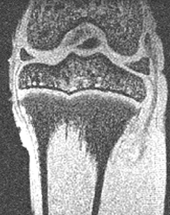

MRI of rabbit knee

Magnetic resonance image (MRI)

and histological section of the

proximal tibia in a young rabbit.

We have evaluated custom MR imaging coils that allow us to characterize the growth of the knee joint in small experimental animals. Comparisons to mechanical testing will help us use these images for development of computational models of the knee joint to study the effect of biomechanics on growth.